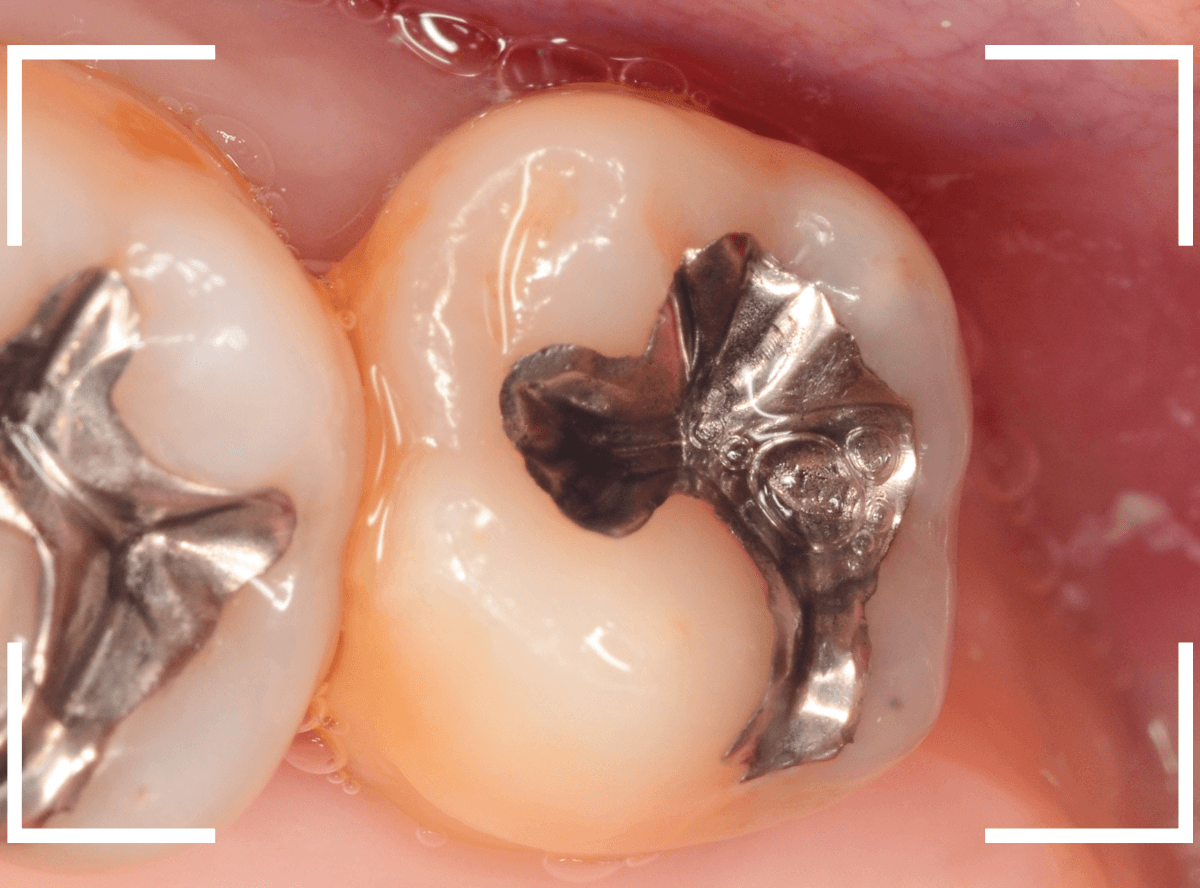

金属を外したところです。

写真では写ってしませんが、この奥に虫歯があります。

全ての虫歯を除去したところです。

抜歯した後ろのおやしらずは、元々虫歯の治療がしてありましたが、その際に抜歯しておいた方が良かったのではないかな、と思いました。